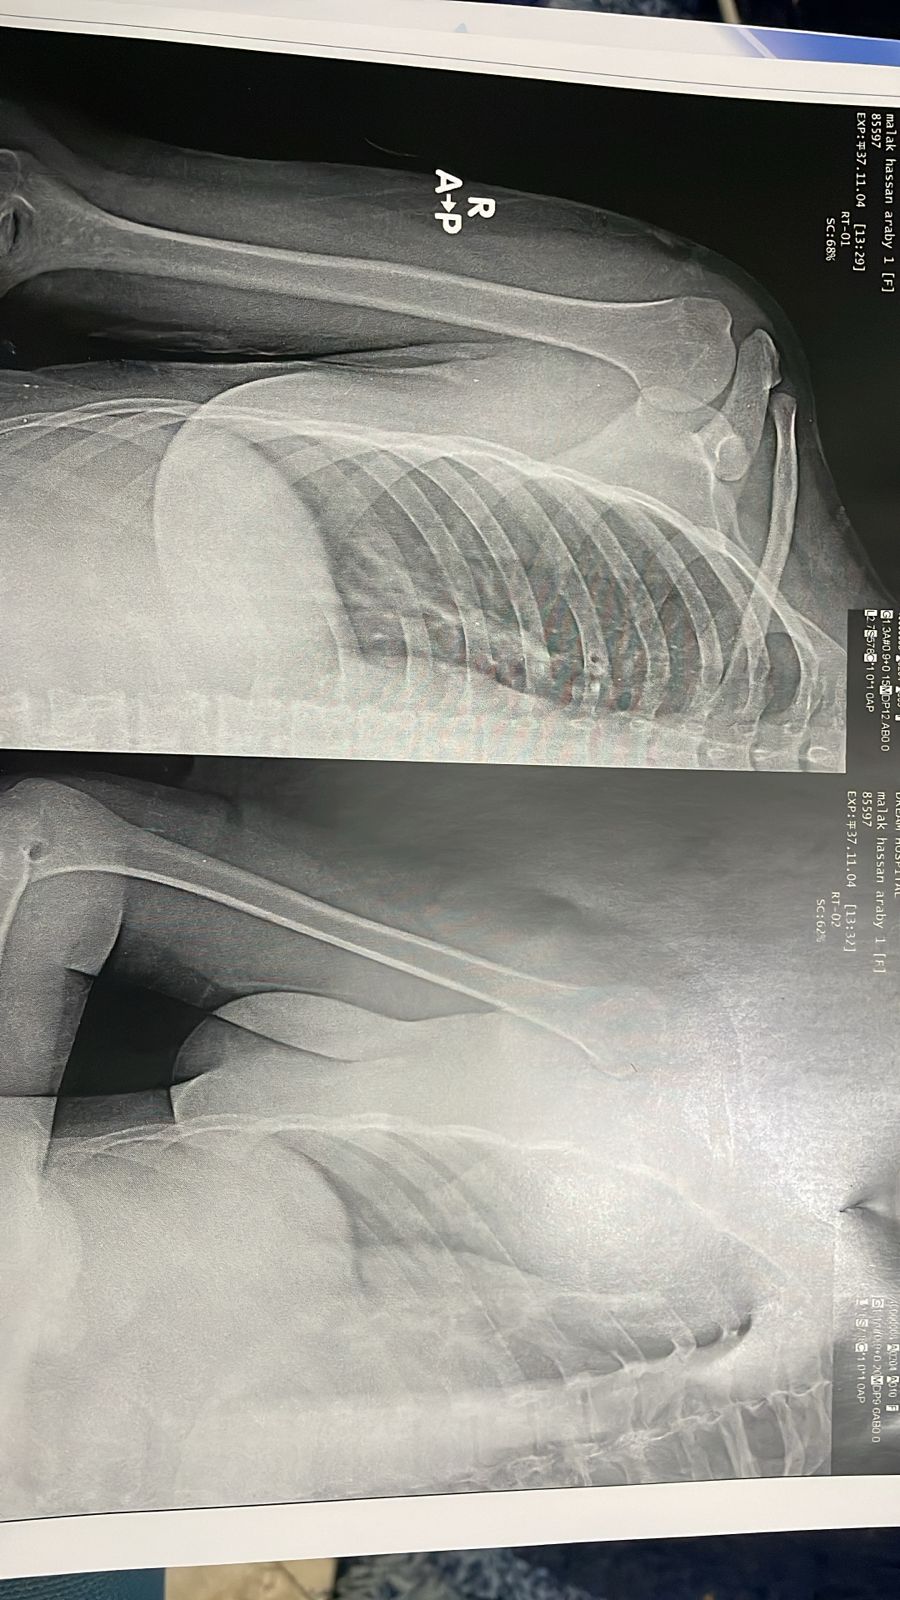

الأشعة الطبية للفتاة

وأوضحت السيدة أن الفتاة نُقلت إلى المستشفى، حيث خضعت لعدد كبير وغير مبرر من الفحوصات، من بينها أشعة على الفقرات والقطنية وأخرى مقطعية، دون إعطائها أي مسكنات.

وتابعت بأنه كان من المفترض البدء بأشعة عادية، ومن ثم استدعاء المزيد من الإجراءات في حالة تطلب الأمر.

وأبدت السيدة استياءها من إدراج مزيد من الفحوصات داخل الفاتورة دون داعٍ، على حد تعبيرها، موضحة أنها فوجئت بمحاولة إجراء أشعة على البطن رغم أن الإصابة كانت في الكتف.